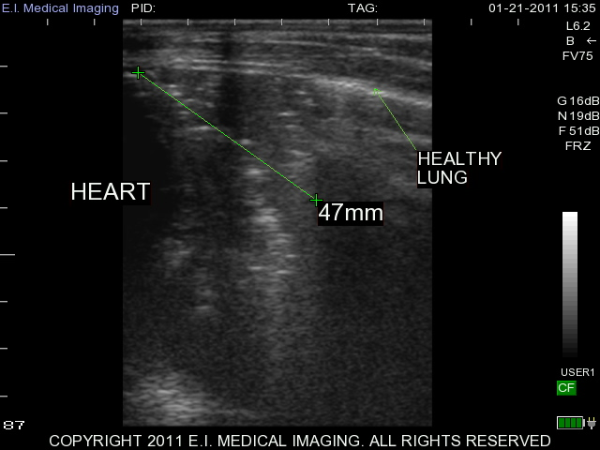

My name is Elizabeth Adams and I am a dairy practitioner in the central valley of California. Recently, I was able to use the IBEX PRO portable ultrasound to look at calf lungs for evidence of damage from calfhood pneumonia. In veterinary school, I scanned all of my patients with respiratory symptoms because it is a fast, non-invasive exam that provides a lot of information quickly. With ultrasound I can see healthy lungs, pleural effusion, atelectasis, consolidation and abscessation.

Ultrasound allows me to look at the surface of the lung; in a healthy lung, this is all we can see as the lung is full of air and doing its job. In a diseased lung, the surface of the lung is abnormal and allows penetration of the ultrasound waves deep into the lung parenchyma. Young calves require only the penetration of a 5-7.5MHz rectal ultrasound probe to see the evidence of damage from previous pneumonia.